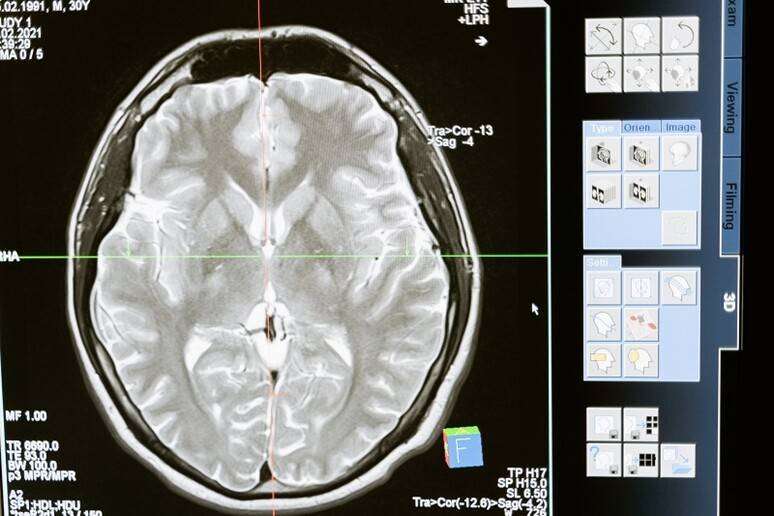

L’epilessia è una malattia neurologica tra le più comuni in età evolutiva e con diversi gradi di gravità, che possono essere imputabili a differenti eziologie, genetiche, strutturali, metaboliche, spesso multifattoriali. Ma oltre a essere caratterizzate da crisi ricorrenti, le epilessie – quelle più gravi e resistenti ai farmaci – secondo gli esperti possono essere associate anche a disturbi nei vari ambiti dello sviluppo neuro-cognitivo del paziente in età evolutiva come, per esempio, disturbi del comportamento, disturbi negli apprendimenti, nella attenzione, nel funzionamento cognitivo e sociale con ripercussioni nell’autostima e nelle relazioni interpersonali.